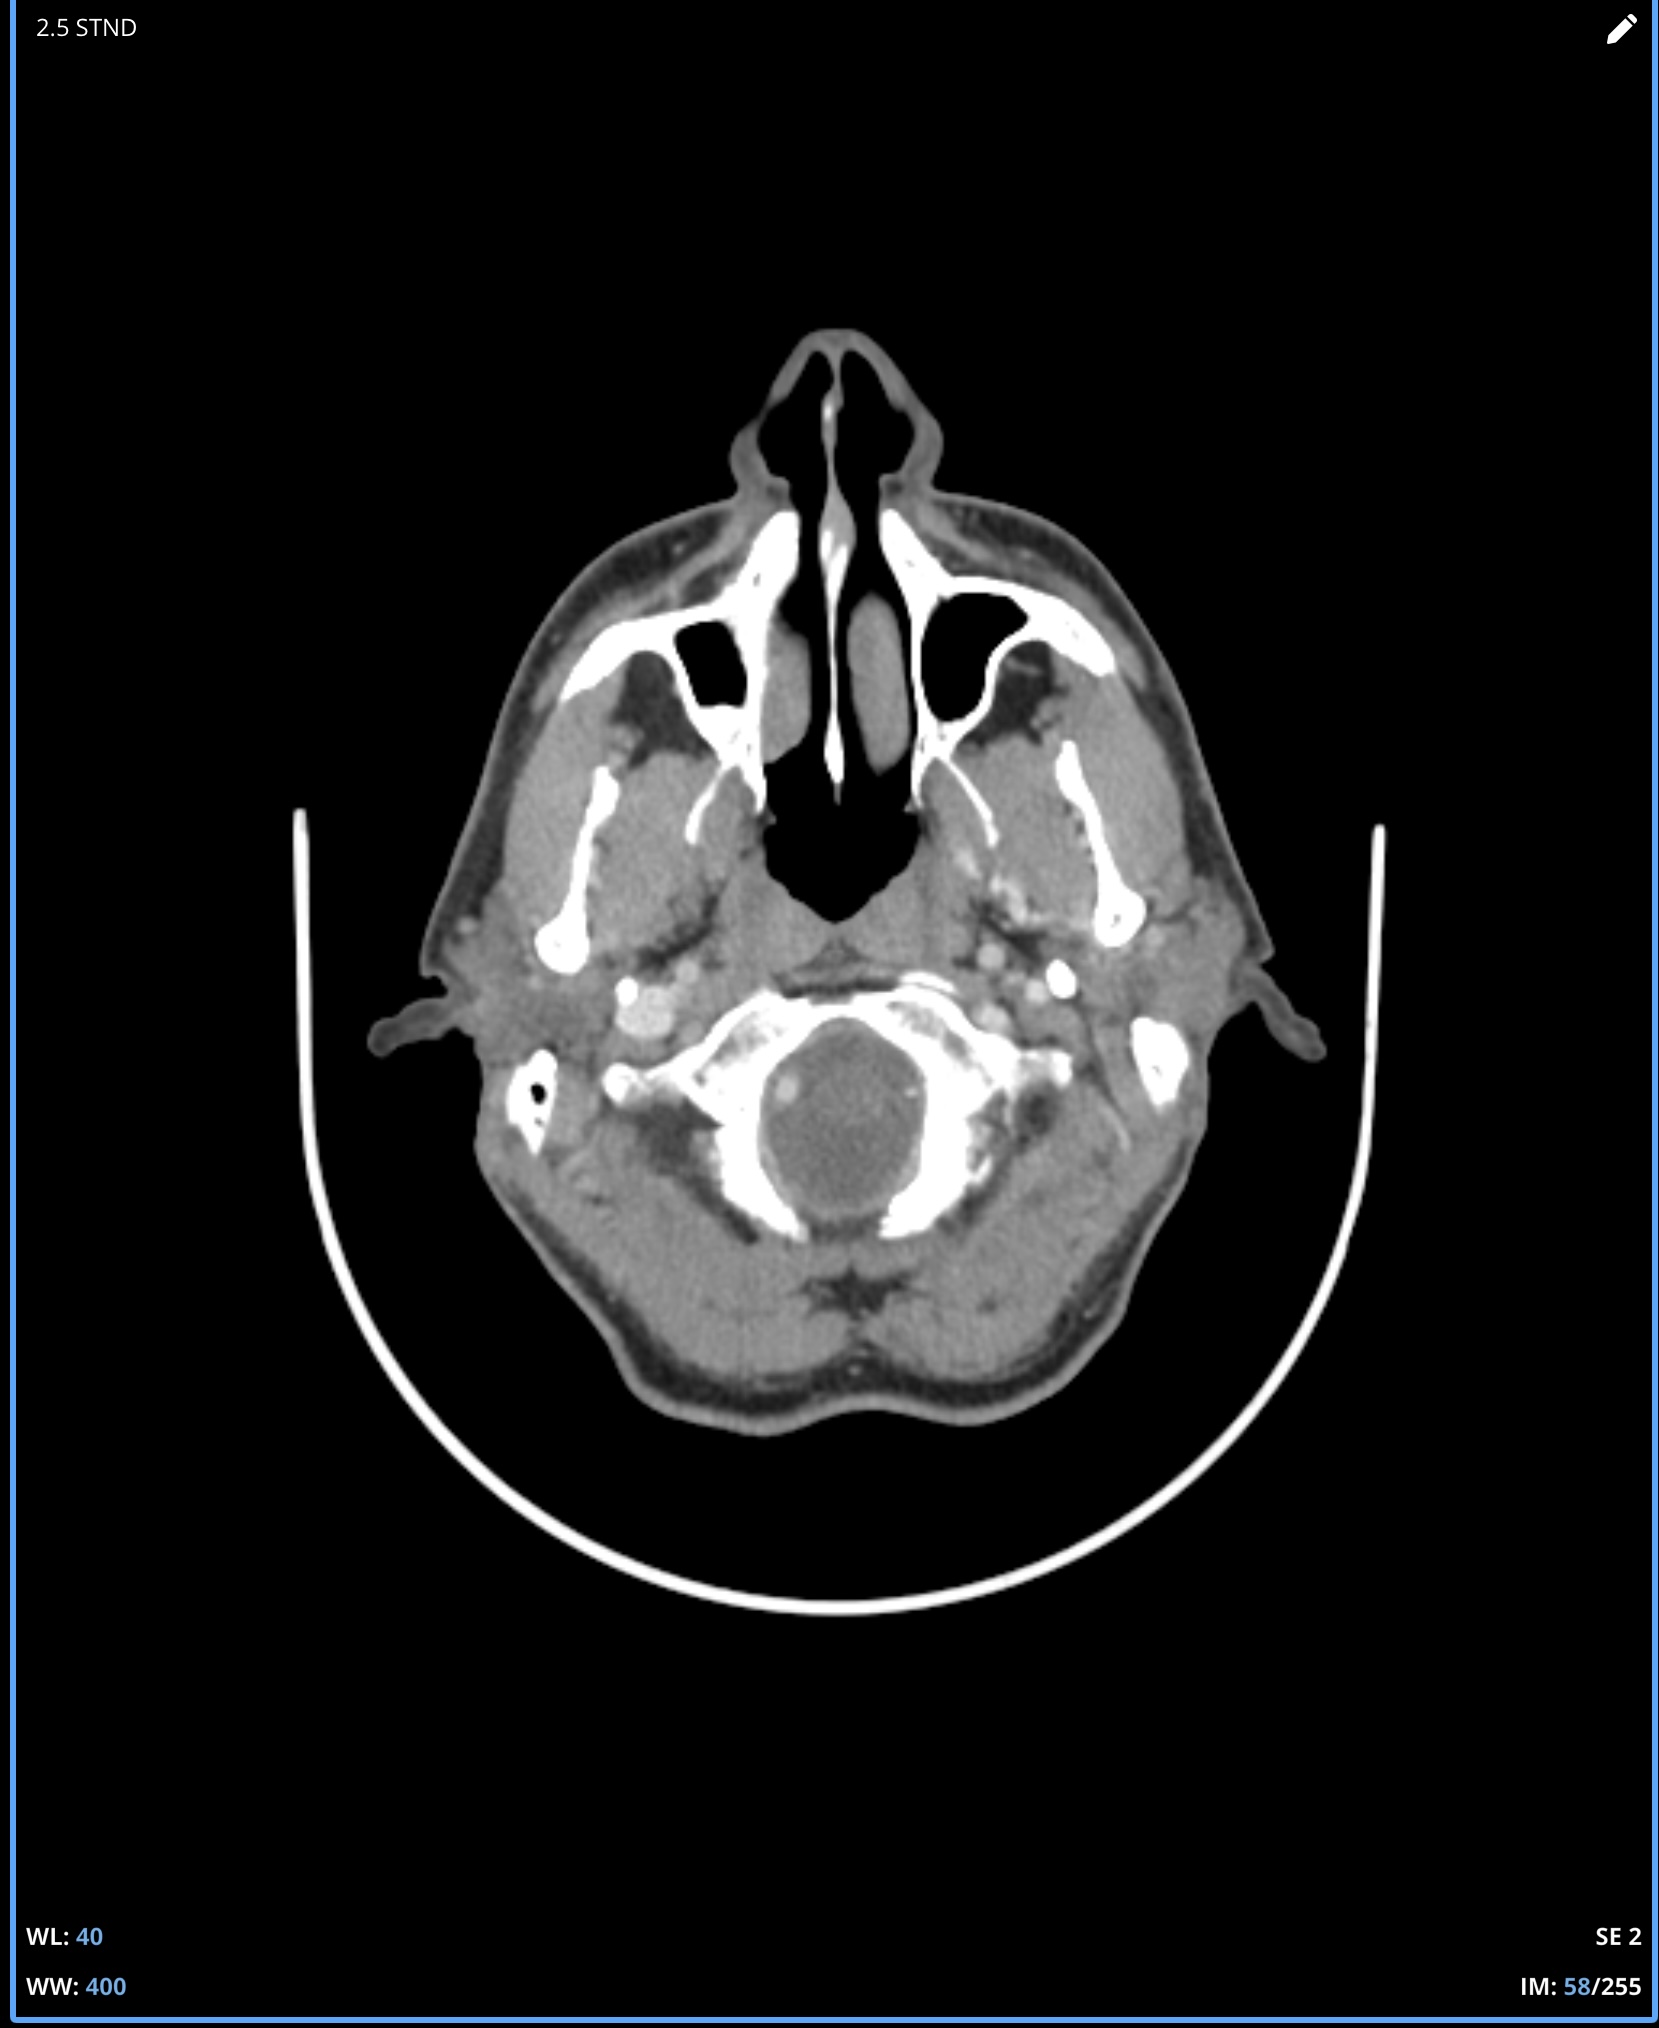

I’m not good at tech so can’t do labels or arrows for your imaging, but on the first two images, there’s clear compression of the IJV between the styloid process & the C1 process. In the first one, it’s not clear whether it’s just the imaging or whether there’s also narrowing of the IJV further down- it disappears so that could be compression but can’t see clearly, if it was compressed there it would indicate TOS which might explain some of your arm symptoms…

In the other two CT images, you can see the styloids really clearly- they’re quite elongated, pretty thick right at the top, and both sides look close to the C1 processes, which is a common place for the IJVs to get compressed.

Re measuring your styloids, firstly measuring is never that accurate as CTs are done in slices so the styloids could be longer than you measured, members often find this after surgery that more is removed than expected! Also even if the measurement is accurate, ‘average’ length styloids are about 2.5cms, although doctors have some funny ideas about what can be normal, we’ve heard of some doctors who think 4cms is! Generally they shouldn’t reach down as far as the C1 process, which yours do…

Where I am in Canada and the healthcare system is slow, I travelled to a different province in November for an updated CT. The report did note a pretty severely squished left jugular between C1 and the styloid and some compression on the right side as well so at least it is acknowledged on a report now. It sure looks like C1 is causing a problem even moreso than the styloid but I am not in a position to figure this out. I can’t help but wonder if I was born this way and it’s actually not the problem at all. Anyway, I would appreciate any feedback whatsoever on these new images….is a C1 shave a must do? I hope this isn’t too many images to post, I was trying to show the full picture of how the compression looks. It is very difficult to pick out the left jugular because it becomes so small:

It’s clear that your right IJV is dominant based on its size vs the left one. I’ve annotated a couple of your 3D images to show what I see & will comment below them. Scrolling through your axial images, it’s obvious you have significant bilateral IJV compression.